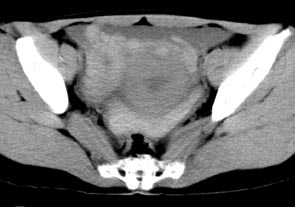

持續性輸卵管妊娠主要表現是保守性手術後下腹痛,偶見腹腔內繼續出血。為停經腹痛陰道流血、盆腔包塊。

血β-HCG的監測是診斷持續性輸卵管妊娠的依據輸卵管妊娠保守性手術後應立即測定血β-HCG為初始值以後每周測2~3次,直到<15mU/ml,如果術後連續監測血β-HCG每周下降<15%時,則持續性輸卵管妊娠的可能性很大。如術後12天血β-HCG下降<10%可以確定診斷。

如保守性手術後患者出現腹痛或腹腔內出血情況,更應警惕持續性輸卵管妊娠的發生。